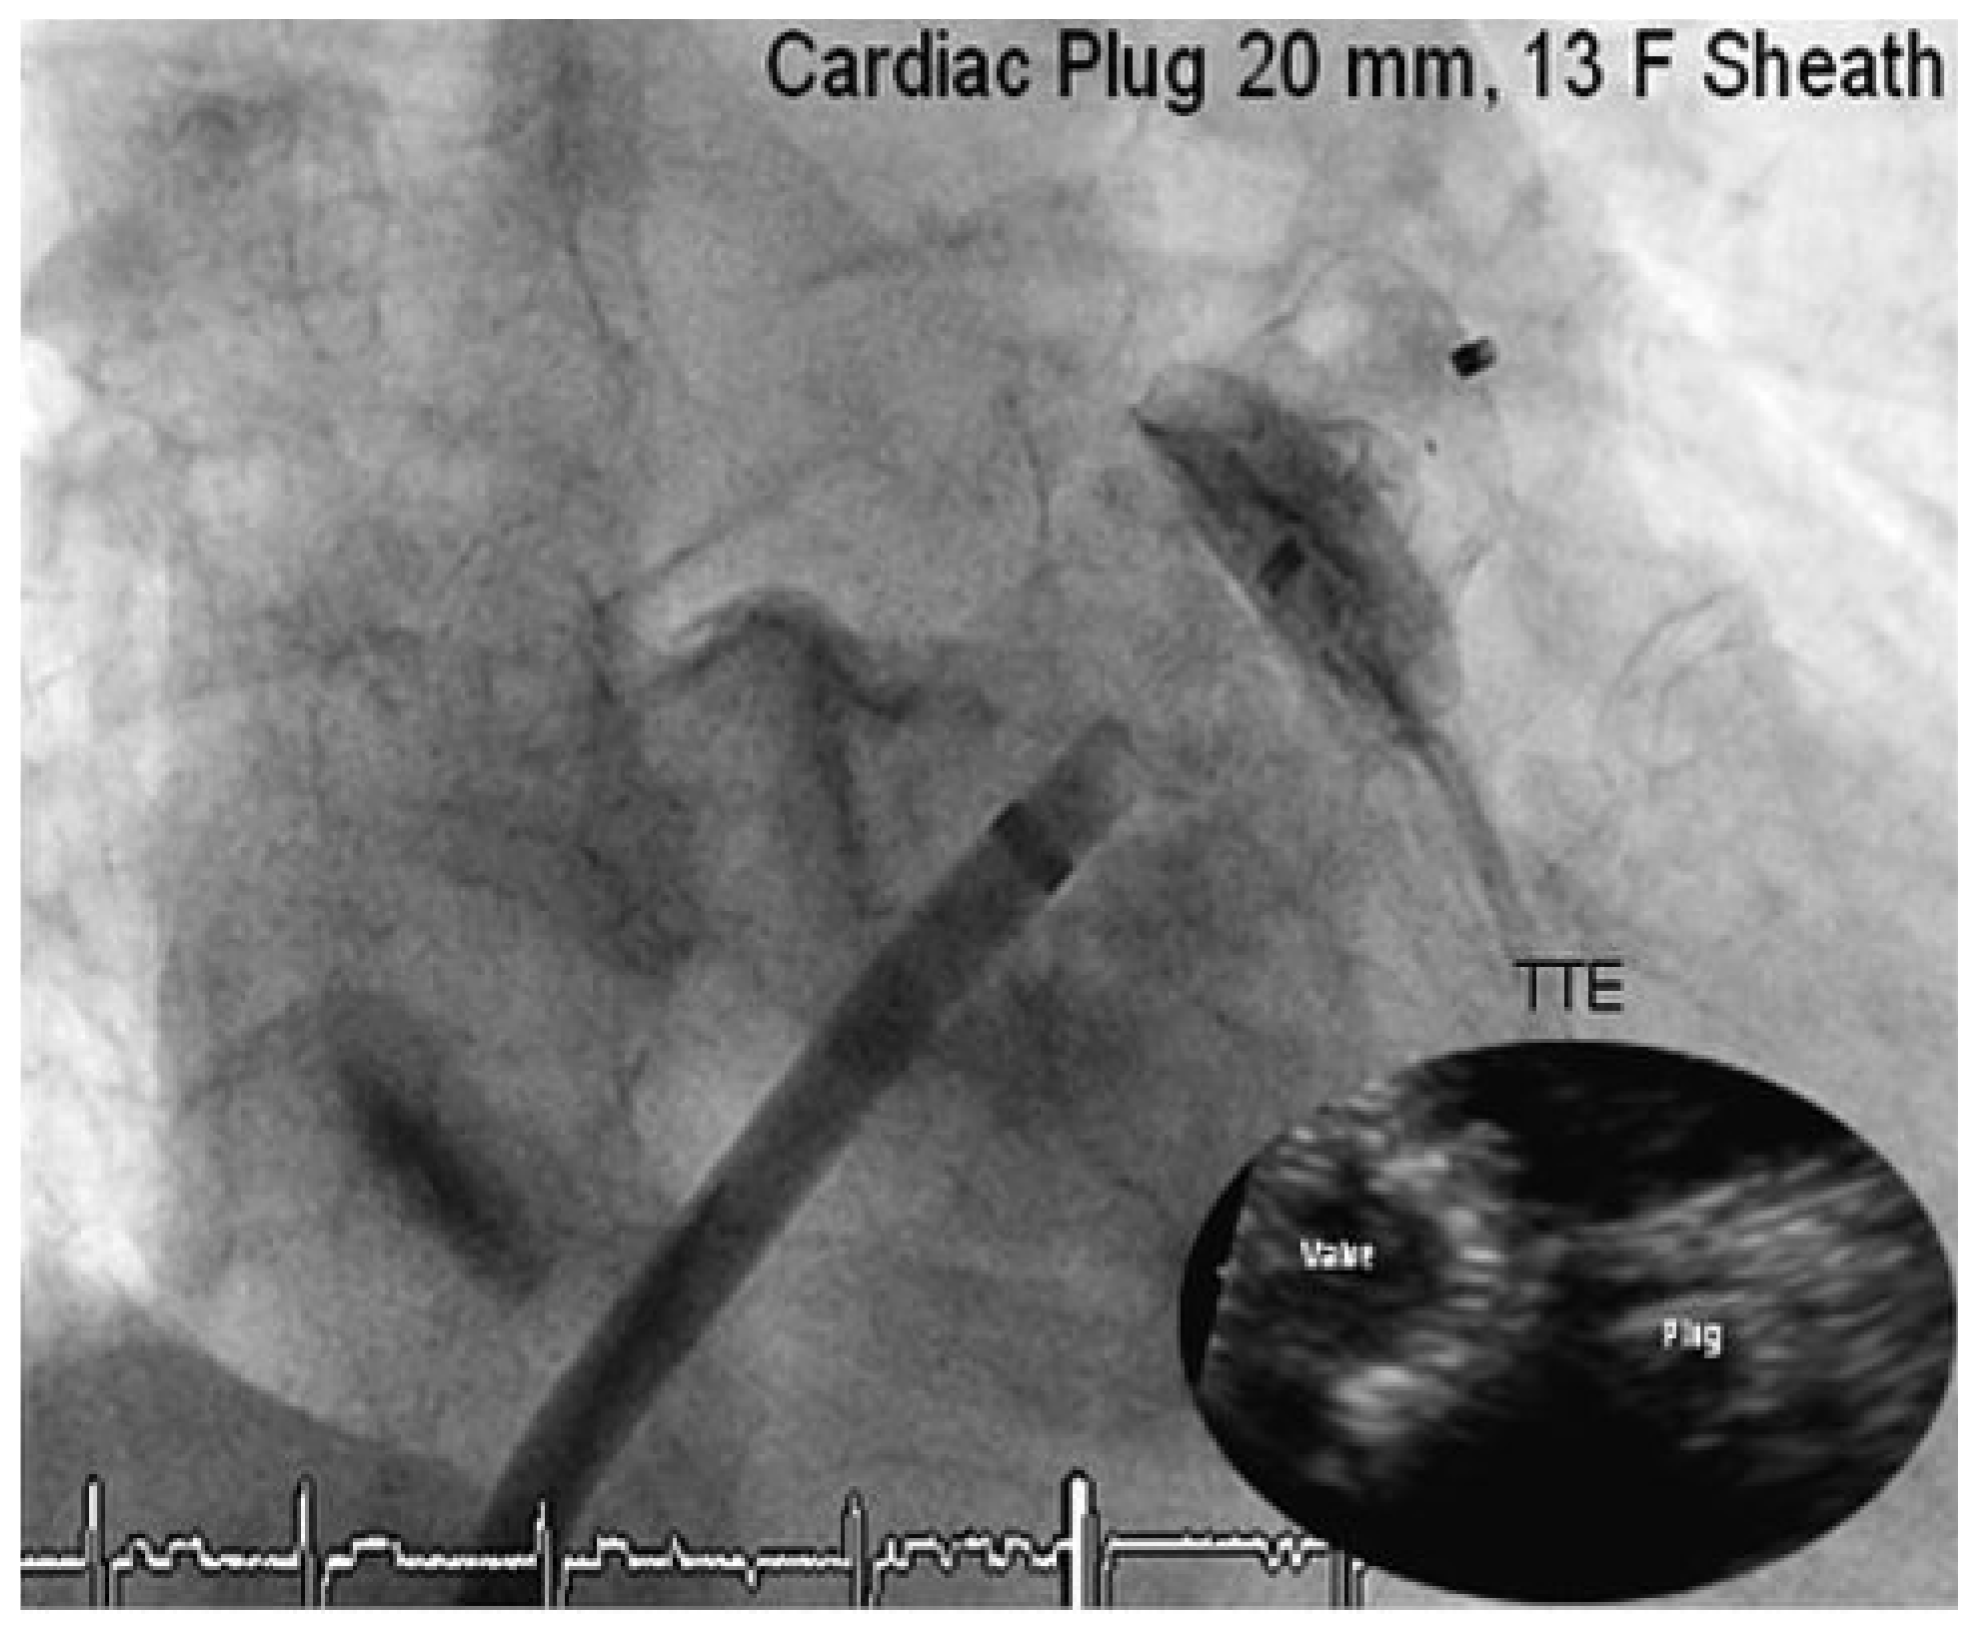

Through a transfemoral venous approach and transseptal puncture, the left atrial appendage was identified and an Amplatzer cardiac Plug 20 mm was positioned in the entry of the appendage. A stable position of the device and complete occlusion of the retroverted, single-lobulated appendage were verified by angiography before the device was released from the catheter (Figure 1 and Figure 2). Thereafter, coronary angiography was performed which showed significant stenosis of the mid left anterior descending coronary artery (LAD) and the proximal left circumflex coronary artery (LCX). Following successful treatment with two everolimus-eluting stents, respectively (Figure 3), angiography of the aorta and iliac artery was performed to measure the aortic valvar annulus and assess the peripheral access site. The patient qualified for implantation of a Medtronic CoreValve bioprosthesis and a 18 French sheath was introduced in the right femoral artery, as well as a temporary transvenous pacemaker through a right jugular access. After balloon dilatation of the degenerative aortic valve with a Nucleus balloon 25 × 40 mm under rapid pacing, the self-expandable bioprosthesis was deployed under fluoroscopic guidance (Figure 4). Periinterventional transoesophageal echocardiography demonstrated an excellent result with negligible paravalvular regurgitation. Simultaneous invasive measurement demonstrated a decrease in the mean transvalvular pressure gradient from 56 to 5 mm Hg. Closure of the right femoral access site was performed under temporary balloon occlusion of the right external iliac artery, from a contralateral femoral access with a Prostar device. The intervention was performed under general anaesthesia.

Figure 2. Angiography and echocardiogaphic control after release of the Amplatzer Cardiac Plug.